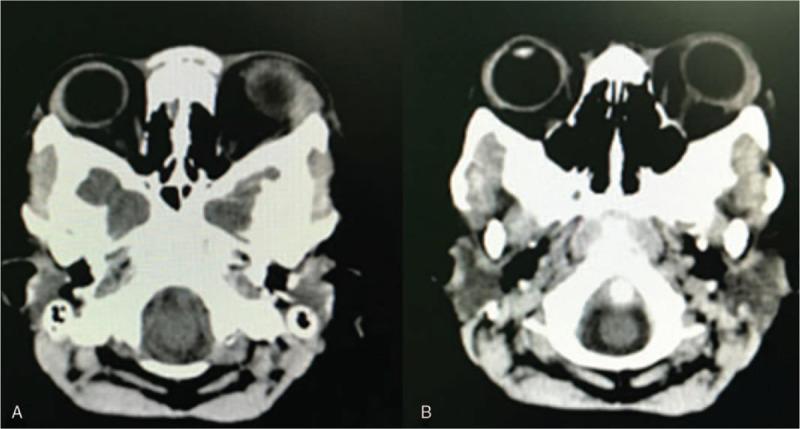

The proptosis and chemosis resolved with no recurrence. No other complications occurred during the follow-up period (12 months), and CT scans revealed that the hematoma had disappeared. The calvarial vault reshaping was satisfactorily performed, and the patient's vision was not impaired.

眼球突出和球结膜水肿消退,无复发。随访期间(12 个月)无其他并发症发生,CT 扫描显示血肿已消失。颅骨穹窿重塑满意,患者视力未受损。

We carried out cranial vault remodeling and fronto-orbital advancement. We applied ophthalmic chlortetracycline ointment on the conjunctivae, elevated the patient's head, evacuated the hematoma, and carried out a left blepharorrhaphy.

行颅穹窿重塑和额眶前移。在球结膜应用四环素眼膏,抬高患者头部,清除血肿,并进行左侧眼睑成形术。